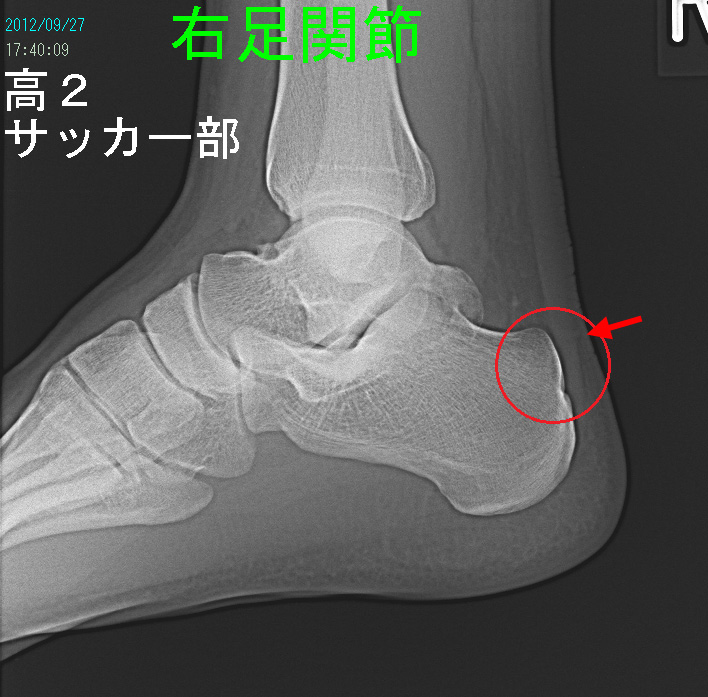

次の症例は17才の高校2年のサッカー部男子生徒です。ゴールキーパーでしたが、平成24年7月中旬に練習試合で右かかとをけられて受傷しました。

翌日からレントゲン像の赤丸部分に痛みが出て、痛みを我慢して練習を続けていたそうです。練習後に痛みは増悪し、安静時痛もあったようです。9月24日から練習を休止し、9月27日当院を受診されました。レントゲン像では異常はありません。赤矢印部に圧痛を認めました。受傷後から2か月も経過していて、痛みが引かないのは単なる打撲ではなく、疲労骨折のような状態になっているのではないかと考え、MRI検査を行いました。